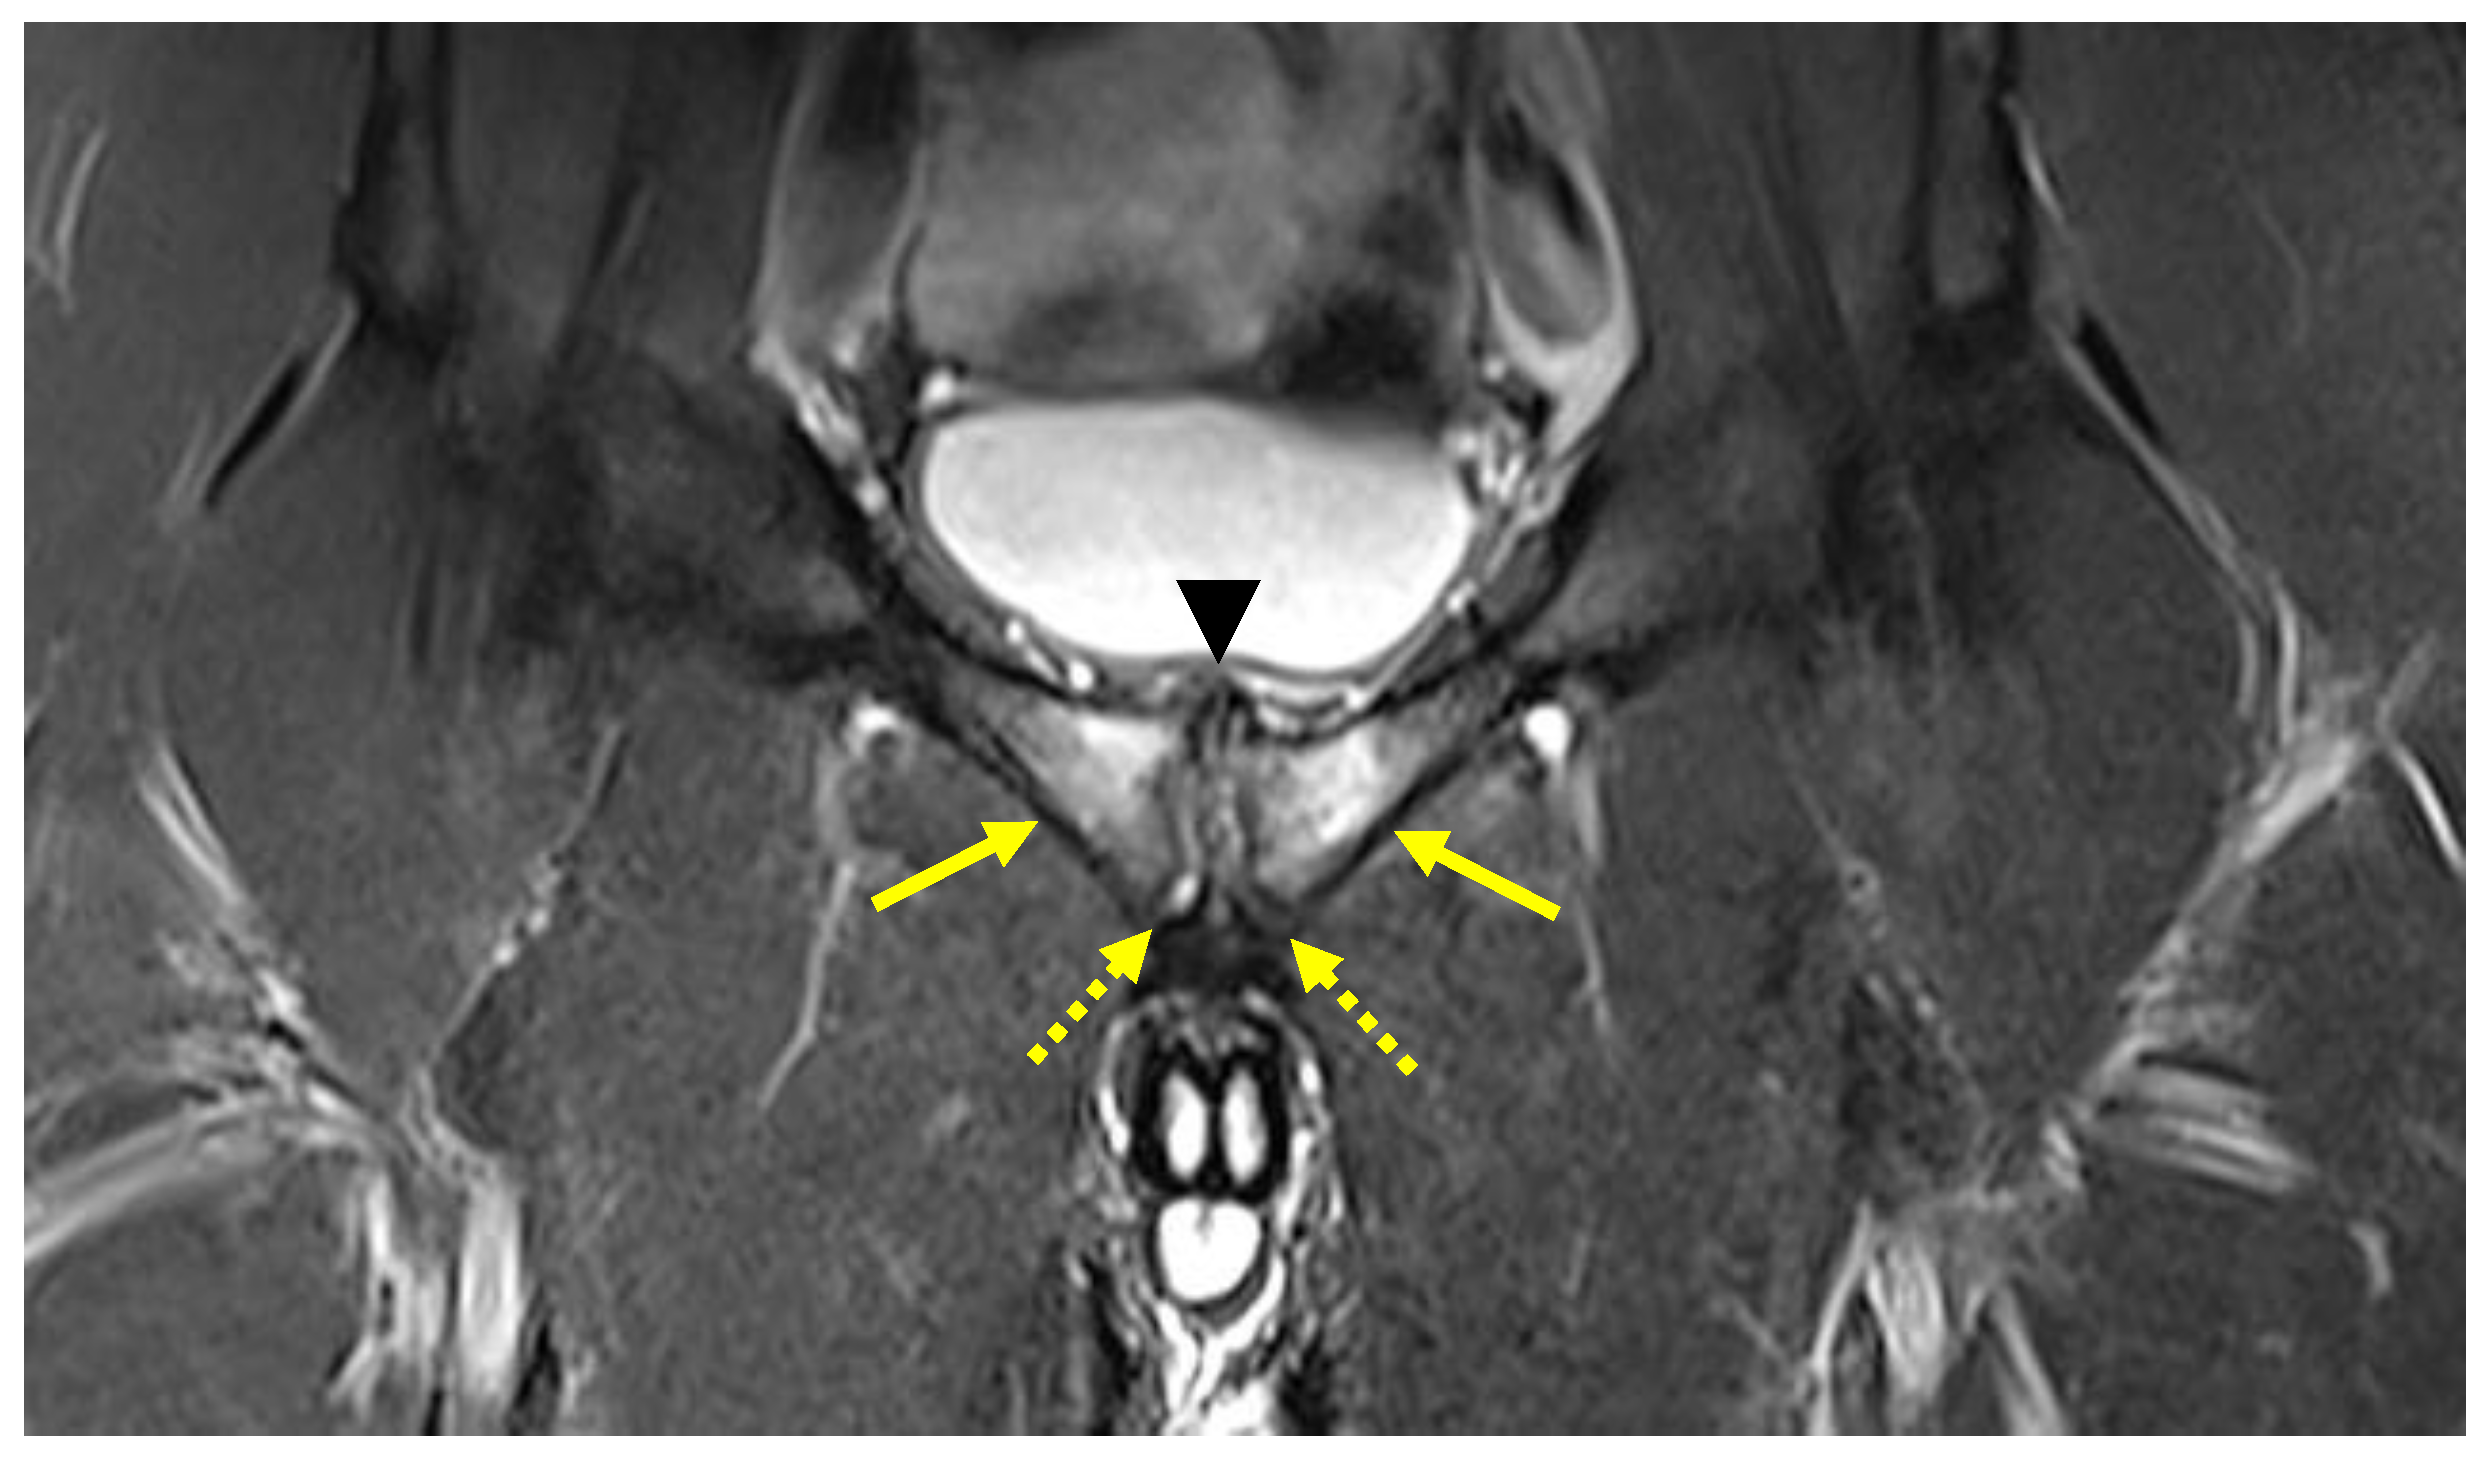

| Secondary inferior cleft sign | Coronal STIR. Axial oblique PD FS | High signal intensity line extending laterally and inferiorly to the lower part of the symphysis, which appears to be in communication with the symphyseal joint space. |

| Secondary superior cleft sign | Coronal STIR. Axial oblique PD FS | High signal intensity line in fluid-sensitive sequences extending parallel to the inferior border of the superior pubic ramus shows connection with the symphyseal joint space. |